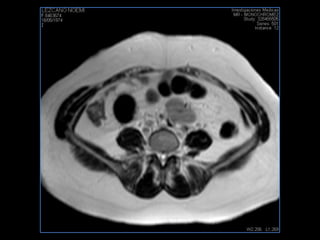

PROTOCOLO abdomen COR T2, AXIAL supresion grasa AX T1 +SAG T2  CON   GADOLINIO :  COR T1+AX T1(DIN) SAT: NO  FASE: RL THK: 6MM  COIL:  GAP: (FACTOR 1.4) 2MM FOV: 40 CM NEX:2 SINCRONIZACION RESPIRATORIA EN 3 O 4 CICLOS ALE